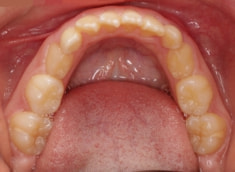

治療後(1年5ヶ月後)

治療開始から11ヶ月